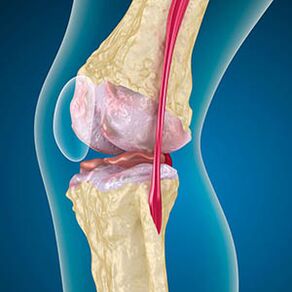

Con artrose, a cartilaxe que forra os bordos dos ósos é abrasión ou está completamente ausente. O tecido danado non é unha fonte de dor, porque non ten receptores. A inflamación nas estruturas próximas provoca síntomas característicos.

O corpo continúa a rexeneración de tecidos danados, pero a cartilaxe crece desigualmente. Como resultado, fórmanse irregularidades que feren outros elementos da articulación. A natureza dos osteófitos explícase por compensación por cartilaxe articular lisa. Outra versión indica que o crecemento de "Spurs" Está asociado a un intento de estabilizar a articulación medialmente ou lateral debido ao debilitamento muscular.